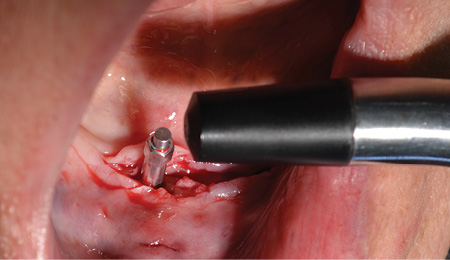

At 13 weeks, the maxillary implants were again tested, and they showed adequate stability to load (figure 12). The implant in the No. 3 position was exposed and ISQ-tested at this time. A 3 mm healing abutment was placed, and the soft tissue was allowed to heal for two weeks (figure 13) prior to placing final abutments and retrofitting the maxillary denture with locator housings.